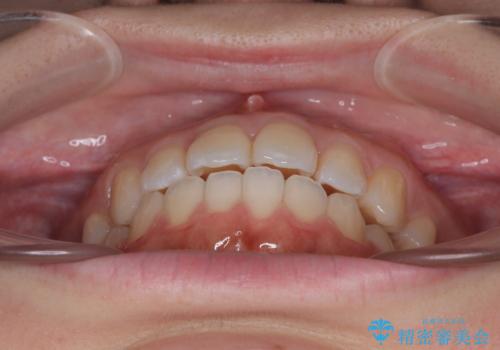

再矯正 開咬に後戻りした歯列をインビザラインで改善

- 矯正治療の後戻りを気にして来院された患者様です。

デコボコと上下前歯の隙間が気になるものの、しっかりと治療をしたいという意思はないとのことで、インビザラインの中でもアライナー数に制約のあるライトパッケージを用いて、治療できる範囲まで歯列を改善していくこととしました。

インビザラインは前歯部の開咬に効果的であることが多く、ライトパッケージにもかかわらず、十分満足のいく仕上がりとなりました。